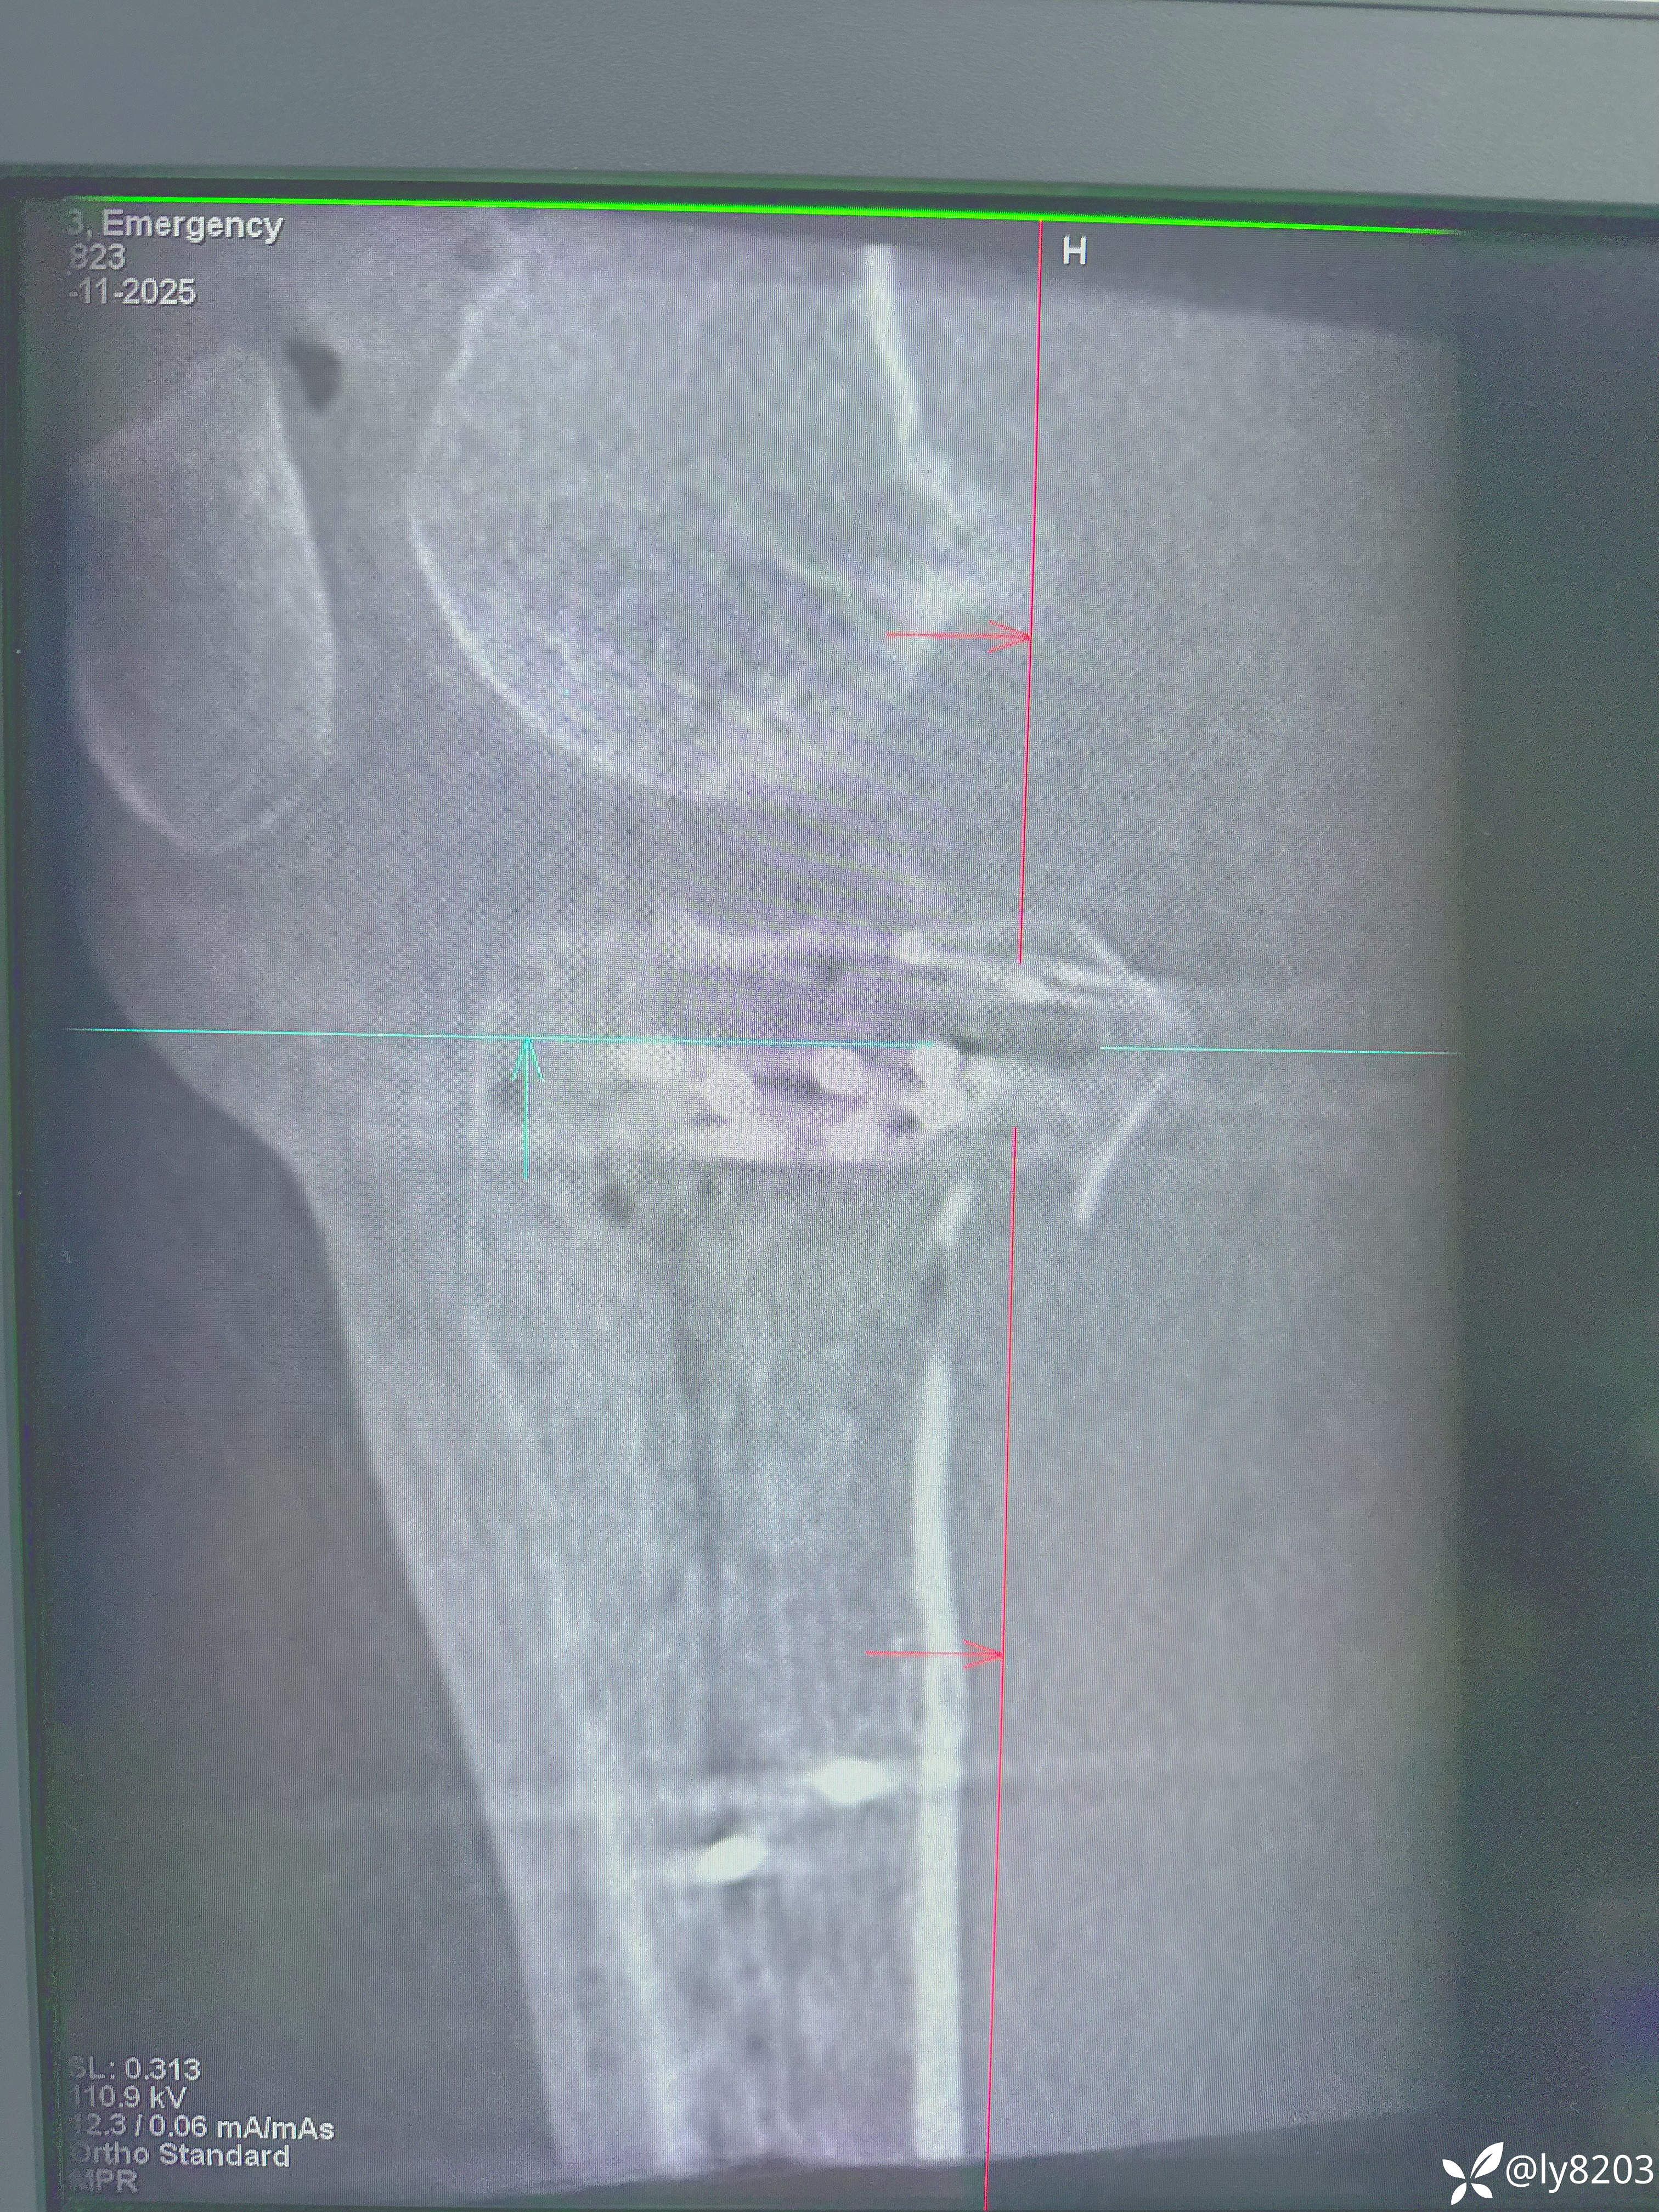

术后影像

术后平片

这个难点在后外侧游离骨块。按胡老师的方法,先将外侧平台用两个弯钳抬起,与前髁间棘对齐后克氏针固定,再从外侧副韧带后缘用骨拨托住并往前顶,从关节线用弯钳从前面抬,没成功,随即改变方案,用胡式顶棒外侧经皮顶,后侧骨块解剖复位,后缘与外侧平台丝滑对齐,克氏针固定。剩下就是常规操作了。以往都是大切口,截骨处理后外侧,胡教授的方法避免了切口大,创伤大。有利于加速康复。